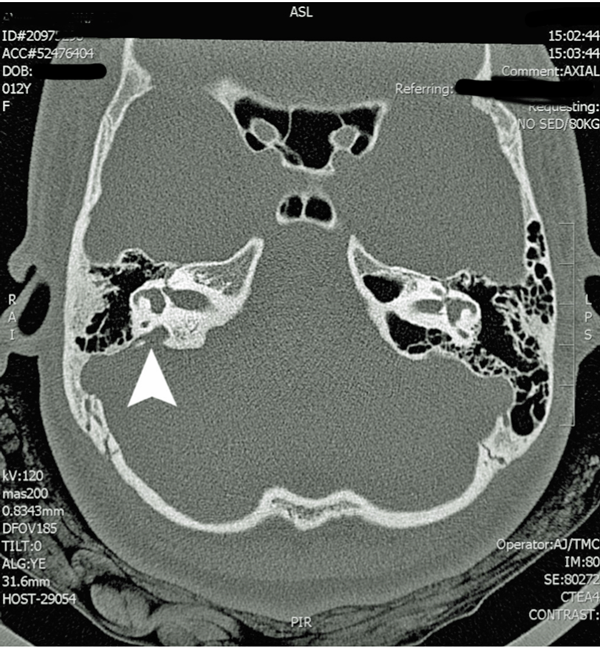

Figure 1: Participant 1 CT scan with arrow pointing to enlarged vestibular aqueduct.

The current gold standard for detecting EVA is through high-resolution computed-tomography and fast-spin echo magnetic resonance techniques that allow the endolymphatic duct and sac to be clearly visualised (Figure 1). The classic radiographic description of large vestibular aqueduct syndrome (LVAS) defines aqueductal enlargement as that diameter exceeding 1.5 mm in an anteroposterior dimension, measured halfway between the common crus and the external aperture [3]. The size of enlarged vestibular aqueducts can vary widely among patients. It is now current practice at many centres to order imaging in children who have a sudden decrease in hearing or who complain of severe dizziness.